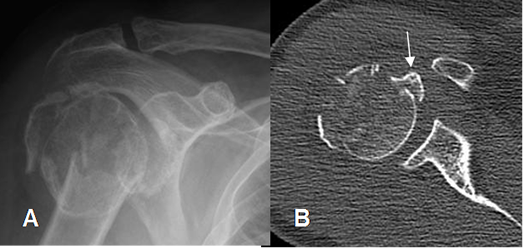

Fig 41. Fractura de la tuberosidad mayor.

A: Rx AP y B: TAC axial. Fractura conminuta y con desprendimiento de la tuberosidad mayor.

Fig 42. Fractura de la tuberosidad menor.

A: Rx AP de hombro. Fractura conminuta e impactada de la cabeza del húmero.

B: TAC axial. Desprendimiento de la tuberosidad menor y subluxación glenohumeral posterior.